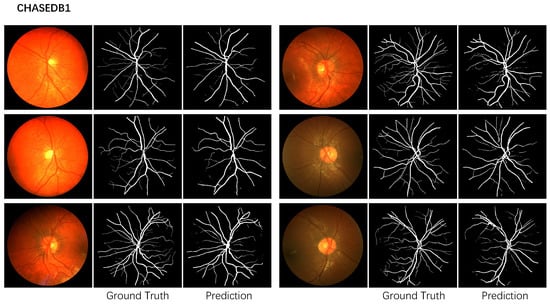

Table 2 shows the performance evaluation on the CHASEDB1 dataset. Figure 4 shows the corresponding prediction. Our method surpasses all the other methods. Yin et al. [17] provide the network with more edge information through a guided filter module. Our multiscale network adopts dual attention to aggregate the relationship between pixels and channels. Our network is built on U-Net and can detect vessels in various shapes and sizes. Our method improves Yin et al. for all the metrics.

Table 2. Segmentation performance of CHASEDB1 inside FOV.

Figure 4. The segmentation example of the proposed method on the CHASEDB1 dataset.